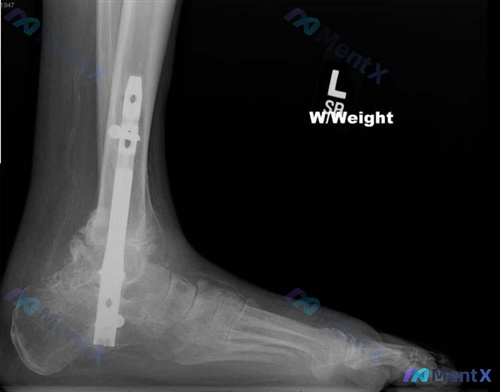

最近看到一个随访病例,资料挺典型,整理一下思路和大家分享。 病例基本情况 - 手术史:因「脚下和脚踝关节炎」(从影像看应该包含距下关节+踝关节骨关节炎)接受了踝关节融合术。 - 主诉:术后出现 脚底麻木,同时伴有 选定区域(包括第四和第五脚/趾)麻木。 影像先看一眼(左踝侧位X光) 影像表现很明确:...